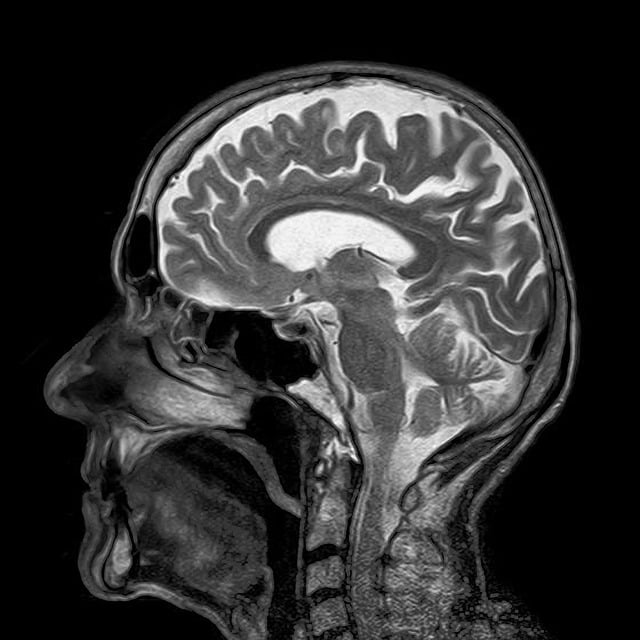

✅ 먼저, MRI 검사란?

MRI(Magnetic Resonance Imaging)는 인체에 해를 주지 않는 자기장을 활용해 몸 안의 조직과 장기 상태를 정밀하게 찍어내는 검사입니다.

CT나 X-ray와 달리 방사선 노출이 없고, 특히 신경계, 관절, 연부조직, 종양 진단에 강력한 효과를 보입니다.

🧠 [1] 뇌 MRI 건강보험 적용 기준

적용 가능 사례

다음과 같은 경우에는 뇌 MRI에 건강보험이 적용됩니다.

- 뇌졸중 의심(급성 두통, 반신마비, 언어장애 동반)

- 외상 후 출혈 가능성

- 뇌종양 의심(시야장애, 복시, 두통, 구토 동반)

- 뇌염, 뇌수막염 등 감염성 뇌질환 의심

- 신경학적 이상소견이 동반된 간질(경련)

💡 TIP: 단순한 ‘두통’만으로는 보험이 적용되지 않습니다. 반드시 신경학적 이상이 의심되어야 하며, CT 촬영 후에도 추가 진단이 필요하다는 의사 소견이 있어야 합니다.